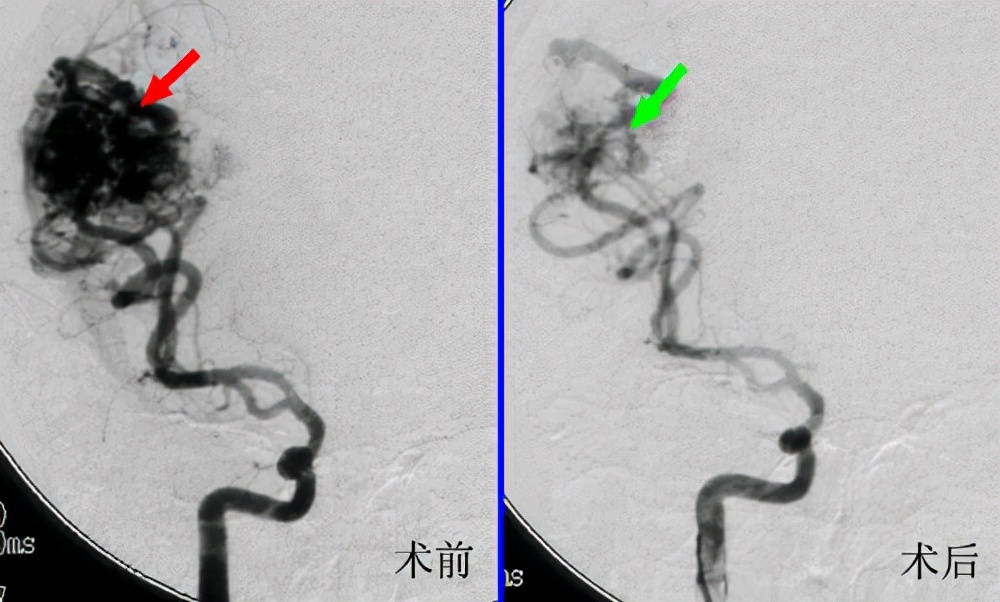

介入栓塞是通过导管选择性地将栓塞剂注人血管畸形区,阻塞大小不等的动静脉瘘,从而达到治疗目的。该方法有创伤小,近期疗效好,可重复性高等优点。 但随着治疗病例的增多,临床上经常遇到单纯供血动脉栓塞后因则支循环建立而复发的报道,因此,越来越多的学者认为单纯供血动脉栓塞治疗领面部AVM,特别是大型瘤体很难彻底治愈。